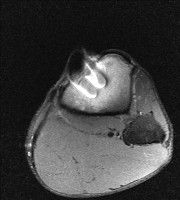

무릎 mri 간단히 봐주실 수 있으시나요 ㅠㅠ

안녕하세요 8년전 십자인대 수술하고 최근 무리한 운동에 무릎 불편감이 생겨서

mri 찍었습니다.

진단결과는 첫 찍은 병원에서 활액막염 이라는 진단을 받았습니다. 혹시 봐주실 수 있으실까요?

올라온 MRI가 단편적이라서 정확한 진단에 어려움이 있지만 십자인대에는 큰 이상이 있지는 않은것 같으며, 무릎관절내 물이 있는 것으로 보아 활액막염의 진단이 맞을 것 같습니다.

하지만 단편적인 영상이기 때문에 촬영병원에서 정확한 판독지 등을 받으시는 것이 좋겠습니다.